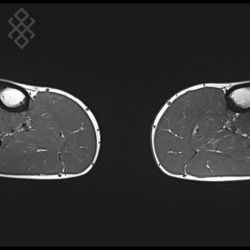

IRM de la Jambe (Mollet)

Vous entrez dans l'aimant, ouvert des 2 côtés, les pieds en premier et allongé sur le dos. Pour recueillir le signal et construire les images, vous aurez antenne sur les jambes. Étant donné que cet examen est bruyant, vous aurez un casque sur les oreilles pour atténuer le bruit de la machine.